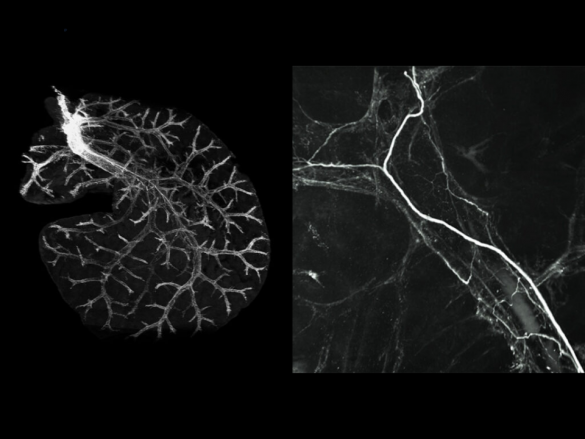

Antes (esquerda) e depois de fígado clareado, submetido a marcador fluorescente – Foto: reprodução do artigo

Através da técnica, os cientistas conseguiram também observar que, para a produção de glicose, o sistema nervoso simpático não se comunica com o fígado diretamente, mas usa as fibras nervosas, que formam uma rede ao longo dos vasos, sem tocar diretamente nas células do fígado (hepatócitos) responsáveis pelas funções metabólicas. “Com isso, a noradrenalina é liberada pelas fibras nervosas do sistema nervoso simpático e chega até o hepatócito por meio de uma rede nervosa que circunda o fígado”, acrescenta Navegantes.